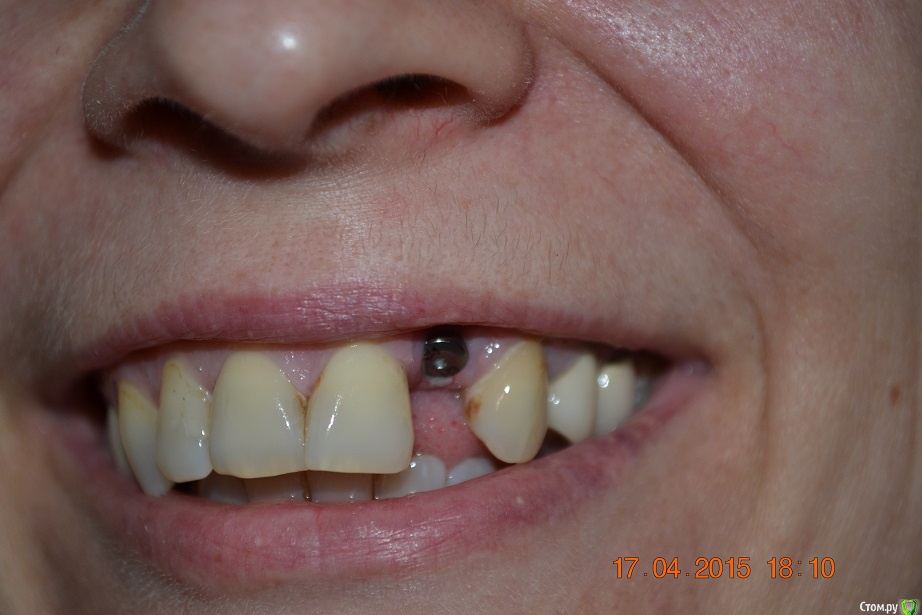

red_butler Опубликовано 17 апреля, 2015 Поделиться Опубликовано 17 апреля, 2015 спасибо, а кто проводит такие операции? сам хирург-имплантолог который ставил имплант? почему сложилась такая ситуация с десной? это моя вина или из-за слишком высокого уровня установки импланта? спасибо.делает хирург который это умеет, да имплант поставлен слегка выше. Покажите фото своей улыбки Ссылка на комментарий

nat-man Опубликовано 17 апреля, 2015 Автор Поделиться Опубликовано 17 апреля, 2015 вот как-то так Ссылка на комментарий

red_butler Опубликовано 17 апреля, 2015 Поделиться Опубликовано 17 апреля, 2015 требуется пластика десны Ссылка на комментарий